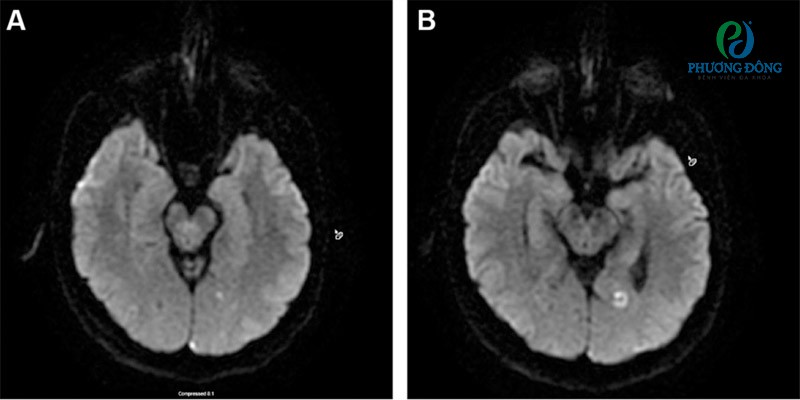

Hình ảnh điển hình của nhồi máu não do chứng đau nửa đầu trên ảnh cộng hưởng từHình ảnh điển hình của nhồi máu não do chứng đau nửa đầu trên ảnh cộng hưởng từ khuếch tán ở một bệnh nhân nữ 45 tuổi mắc chứng đau nửa đầu mạn tính có kèm theo triệu chứng tiền triệu.